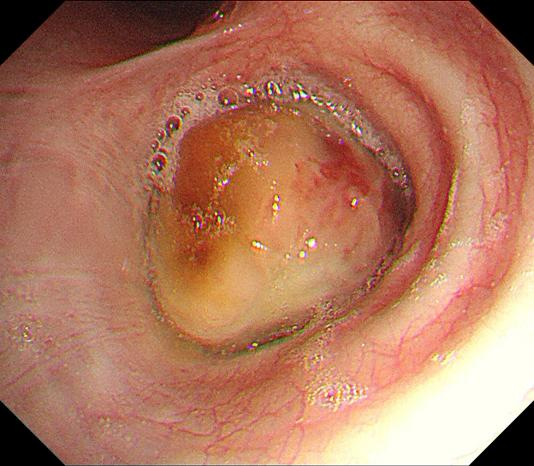

王先生完全被腫瘤堵塞的右主支氣管

但在王先生的麻醉、供氧等治療上卻困難重重:右主支氣管完全堵塞,需要在氣管鏡下應(yīng)用激光消融治療一點(diǎn)一點(diǎn)燒灼、一寸一寸“打通”,耗時(shí)長(zhǎng)、風(fēng)險(xiǎn)高,要求患者能夠絕對(duì)制動(dòng),所以最好是能在全身麻醉的狀態(tài)下進(jìn)行。